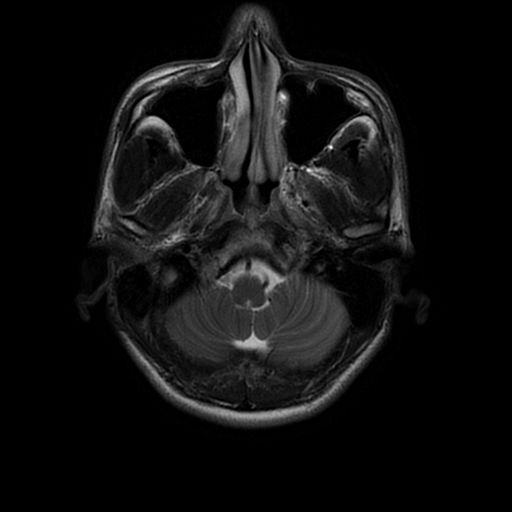

术前影像

入院后行术前检查,核磁共振显示:斜坡偏左占位,脑膜瘤可能性大。

左侧斜坡脑膜瘤